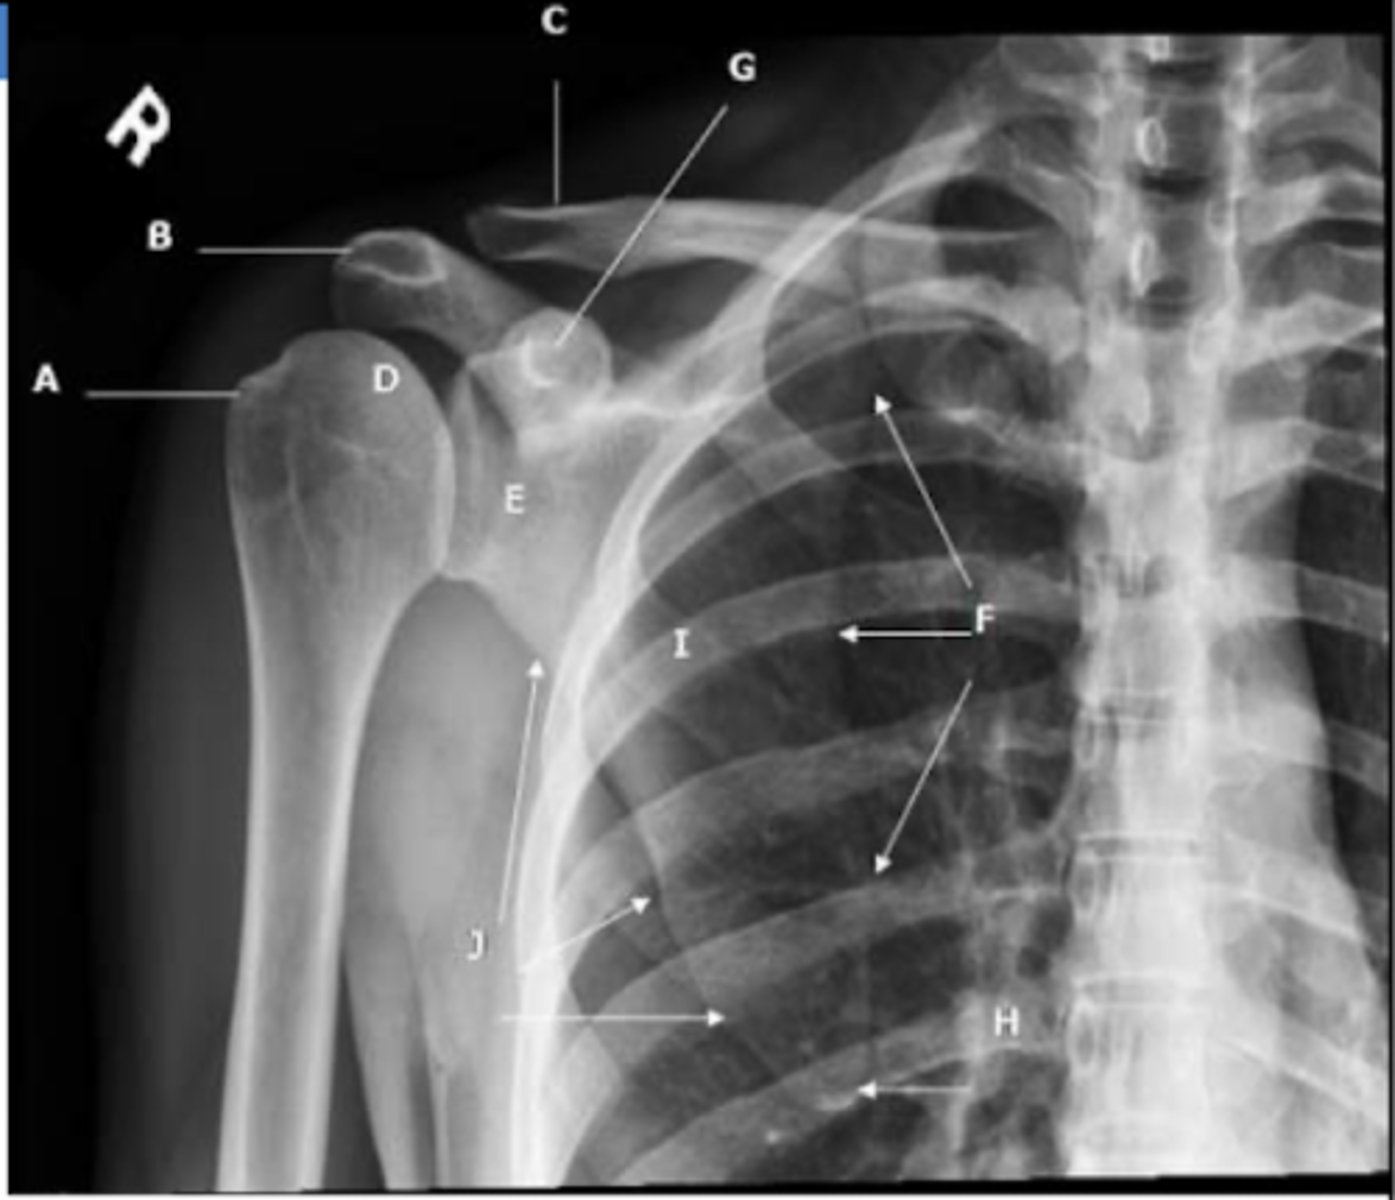

REVIEW: Shoulder XR (AP view - III)

A → greater tubercle

B → acromion

C → clavicle

D → humeral head

E → glenoid process

F → medial/vertebral border of the scapula

G → coracoid process

H → inferior angle of scapula

J → axillary/lateral border of scapula